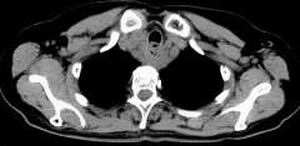

女,61岁,吞咽困难(包括开水)已久。

食道中上段癌并锁骨上窝淋巴结转移.

食道中上段中分化鳞癌伴锁骨上淋巴结转移